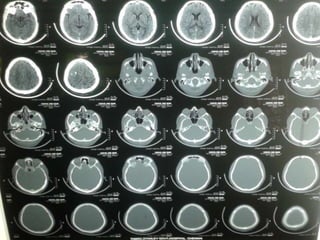

CT-BRAIN REPORT

 CT BRAIN AXIAL SECTIONS SHOWING

1. HYPERDENSITY IN THE RIGHT FRONTAL

REGION

2. HYPERDENSITY IN THE R TRANSVERSE

SINUS

3. HYPODENSITY IN THE SUPERIOR SAGITTAL

SINUS (?EMPTY DELTA SIGN)

 SUGGESTIVE OF ?PARENCHYMAL

HEMORRHAGE WITH CORTICAL VEIN

THROMBOSIS ?CALCIFIED GRANULOMA.

1

22

3